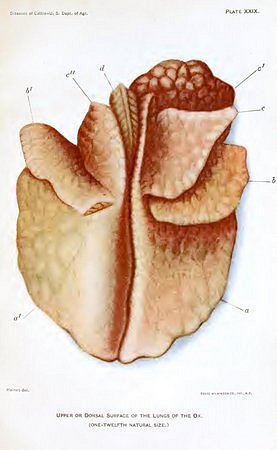

| XXIX. Upper or dorsal surface of the lungs of the ox | 368 |